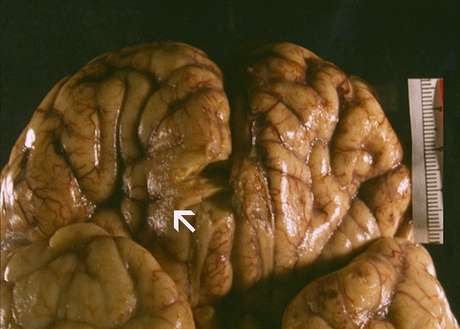

As infecções com a ameba - conhecida como Naegleria fowleri, pelos cientistas - são raras, mas quase sempre mortais. Entre os anos de 1962 e 2014, apenas 132 pessoas foram infectadas. Destes, só três sobreviveram.

Especialistas alertam que a ameba - que se alimenta do tecido cerebral - se reproduz em água morna. Portanto, uma piscina gelada ou um banho frio podem ajudar a evitar a infecção.